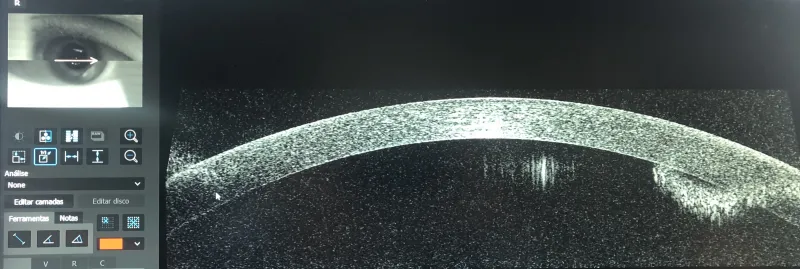

Com dois consultórios e equipamentos de última geração, a clínica conta com uma estrutura ágil e eficiente para atender às diversas necessidades oftalmológicas dos pacientes.

A equipe da AORP é composta por médicos oftalmologistas especialistas em diversas áreas, tais como retina e patologias refrativas.